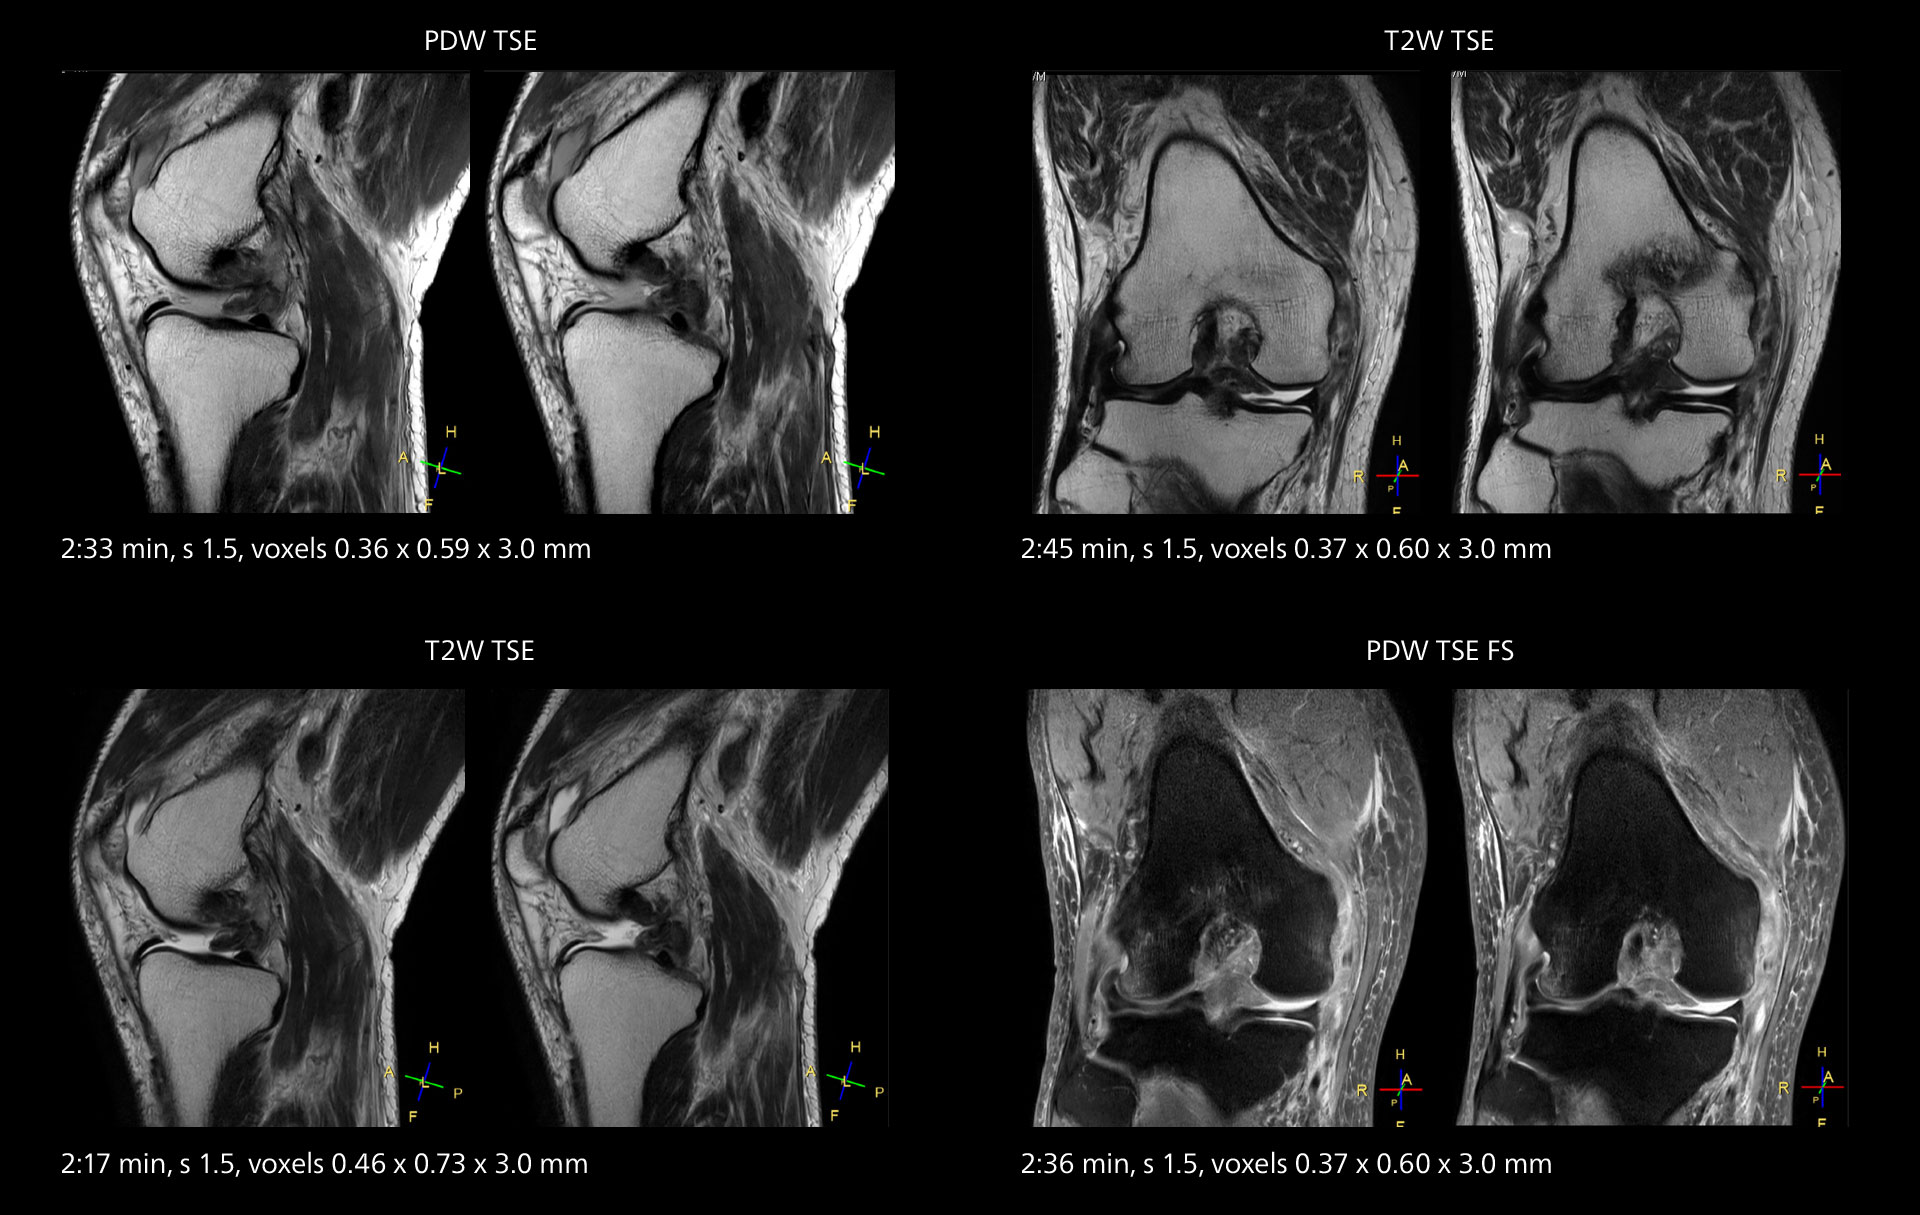

MRI of the knee

Images showing a posterior cruciate ligament (PCL) tear, a detached medial collateral ligament (MCL) on the tibial side and an intact anterior cruciate ligament (ACL). SmartPath to Elition X helped reduce scan time compared to previous imaging while maintaining resolution.

MRI of the knee

Images showing a posterior cruciate ligament (PCL) tear, a detached medial collateral ligament (MCL) on the tibial side and an intact anterior cruciate ligament (ACL). SmartPath to Elition X helped reduce scan time compared to previous imaging while maintaining resolution.

Sannodai Hospital radiologists had been very satisfied with their Ingenia 3.0T with Compressed SENSE, however after acquiring SmartPath to Elition X they have demonstrated improved image quality and even higher speeds in imaging studies throughout the body, according to Dr. Makuuchi. “Generally, we were impressed by seeing that images are very sharp and have higher SNR than we used to get with our Ingenia 3.0T system,” he notes. “We were delighted to see that high image quality can be obtained in a short time thanks to the Elition with its powerful An example of increased imaging speed is in knee studies. “There is a definite scan time reduction for T2* mFFE and proton density TSE – both of these sequences benefit from much shorter repetition times,” he reports.

gradients. Some high resolution examinations that were not possible before dueto their longer scan time, are now routinely performed with the upgraded system.”